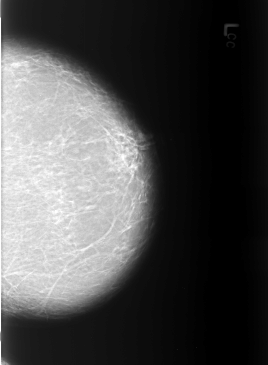

B_3228_1.LEFT_MLO

LEFT_MLO LINES 5744 PIXELS_PER_LINE 3992 BITS_PER_PIXEL 12 RESOLUTION 50 NON_OVERLAY

FILE: B_3228_1.RIGHT_MLO.OVERLAY

TOTAL_ABNORMALITIES 1

ABNORMALITY 1

LESION_TYPE MASS SHAPE ASYMMETRIC_BREAST_TISSUE MARGINS N/A

ASSESSMENT 2

SUBTLETY 4

PATHOLOGY BENIGN_WITHOUT_CALLBACK

TOTAL_OUTLINES 1

BOUNDARY